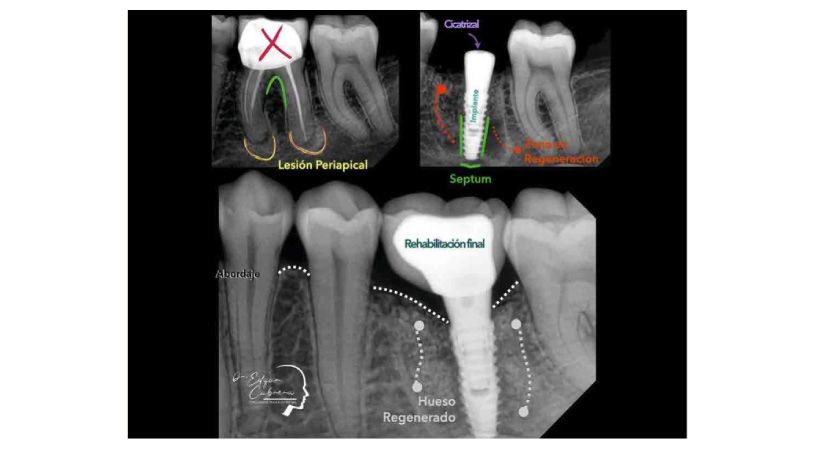

La técnica Socket-Shield

Planificación digital, cirugía guiada y carga inmediata de implantes: seguimiento de 2 años